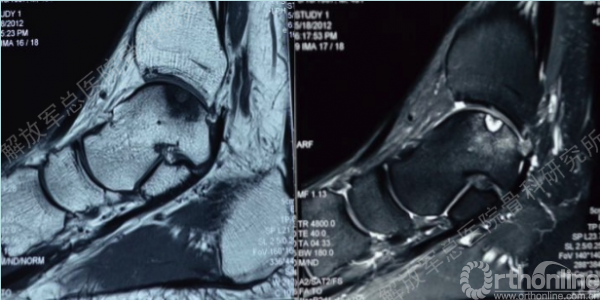

甄某,男,38岁,右侧距骨软骨损伤(运动伤)。

同样距骨软骨损伤完全可以利用第四代组织工程软骨进行修复,经过MRI检查可以诊断损伤部位,范围。此例患者软骨损伤存在软骨下骨板破坏及骨缺损。